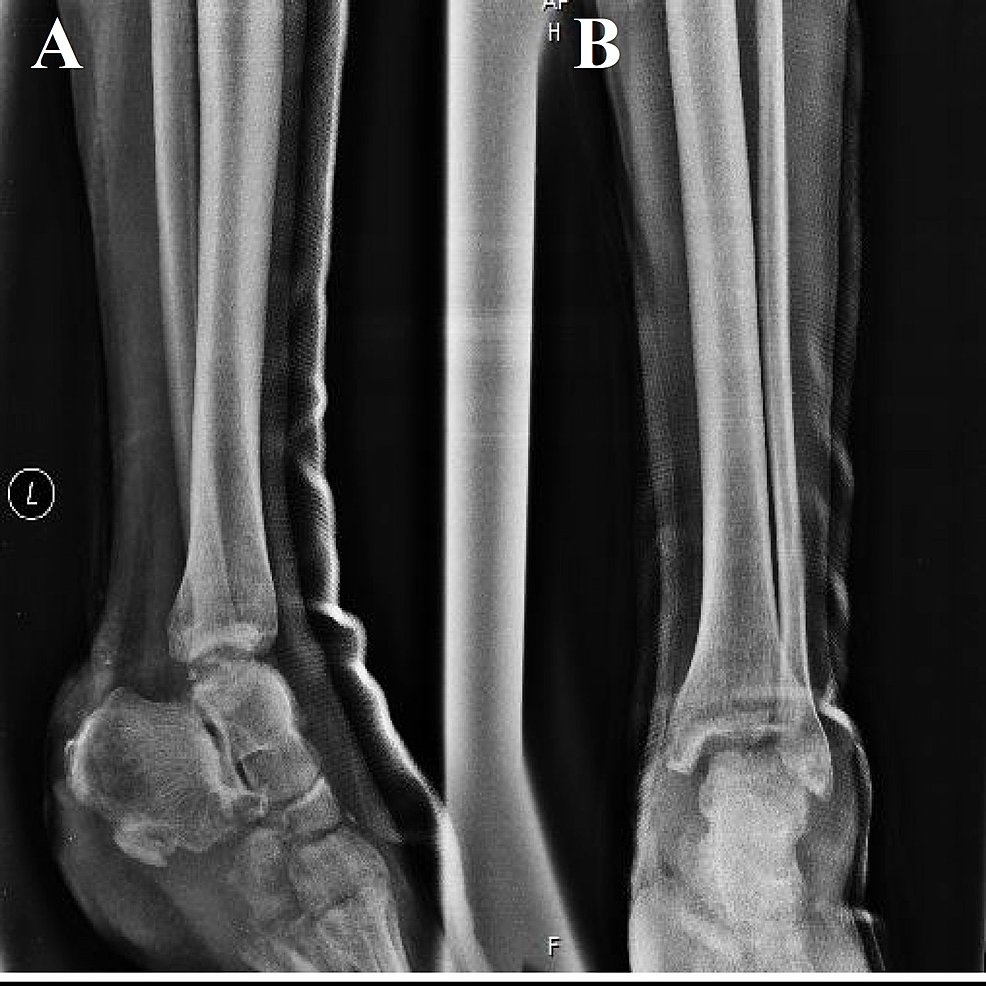

From www.mdpi.com

Applied Sciences Free FullText Detecting Ankle Fractures in Plain Foot Crush Injury Without Fracture crush injuries to the foot are a rare occurrence and often result from major trauma. a foot crush injury is a severe type of broken foot condition. severe crush injury increases the risk for organ failure and death due to the possible development of crush syndrome,. foot compartment syndrome is a devastating lower extremity condition where. Foot Crush Injury Without Fracture.